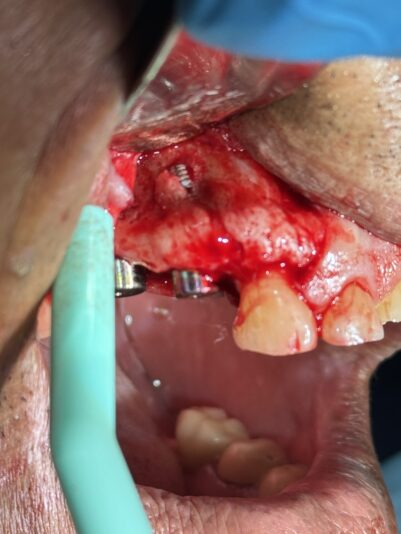

• This case was a tricky one. Sometimes, we just need to do the best with what our patients anatomy gives us. Patient was referred to me wanting an implant and there wasn’t much to work with and oh yeah, the mental foremen was smack dab in the middle of our sight.

With the help of some buccal plate decorticating, a tenting screw, and some CGF/PRF…

Read more